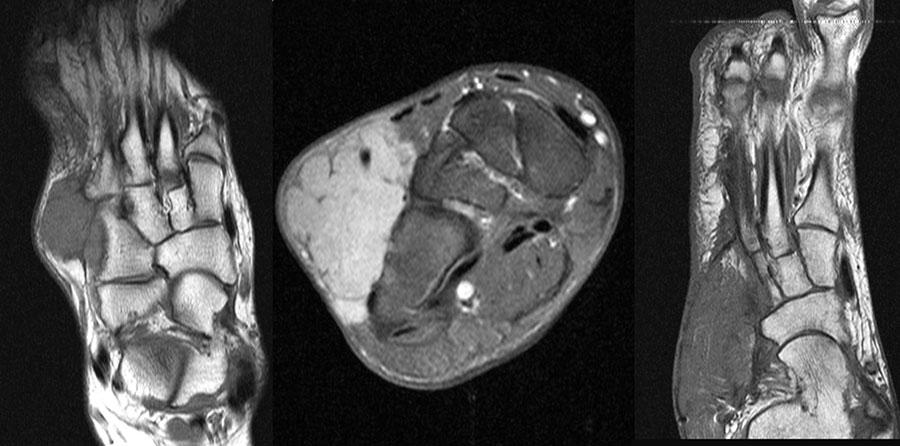

MR-tomographische Darstellung eines unspezifischen weichteiligen Raumforderug im Bereich des dorso-lateralen Rückfußes. Die offene Probebiopsie ergab schließlich die Diagnose eines hochmalignen Synovialsarkoms.

Abbildung 34

10% aller Patienten mit Weichteilsarkomen weisen bei Erst­diagnose bereits Metastasen auf, meist in der Lunge. Drei Viertel der Weichteilsarkome zeigen eine schlechte histo­logische Differenzierung („high-grade“, G3 und G4) und die Letalität beträgt insgesamt über 30%. Trotz des vergleichs­weise seltenen Vorkommens (<1% aller Malignome) gilt diesen Entitäten aufgrund der schlechten Prognose erhöhte Aufmerksamkeit. Das Synovialsarkom ist der häufigste maligne Weichteiltumor im Bereich des Fußes und betrifft hier typischerweise Adoleszente und Erwachsene in der 2. bis zur 5.Lebensdekade (Abb. 34). Zwischen Beginn der Symptome und endgültiger Diagnose­stellung vergehen durchschnittlich 21 Monate. Das Synyovialsarkom zeigt einen unspezifischen klinischen Verlauf mit variabler Wachstumsge- schwindigkeit und kann zahlreiche andere Entitäten imitieren 50. Die Gefahr sowohl pulmonaler/hämatogener als auch lymphogener Metastasen ist hoch.